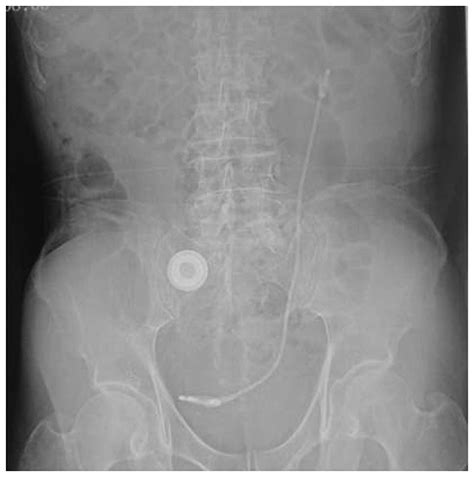

Лечение стриктуры мочеточника - отзыв нашего па...

Мочеточник У Женщин Расположение Фото Воспалени...

Как Выглядит Мочеточник У Женщин Снаружи Фото –...